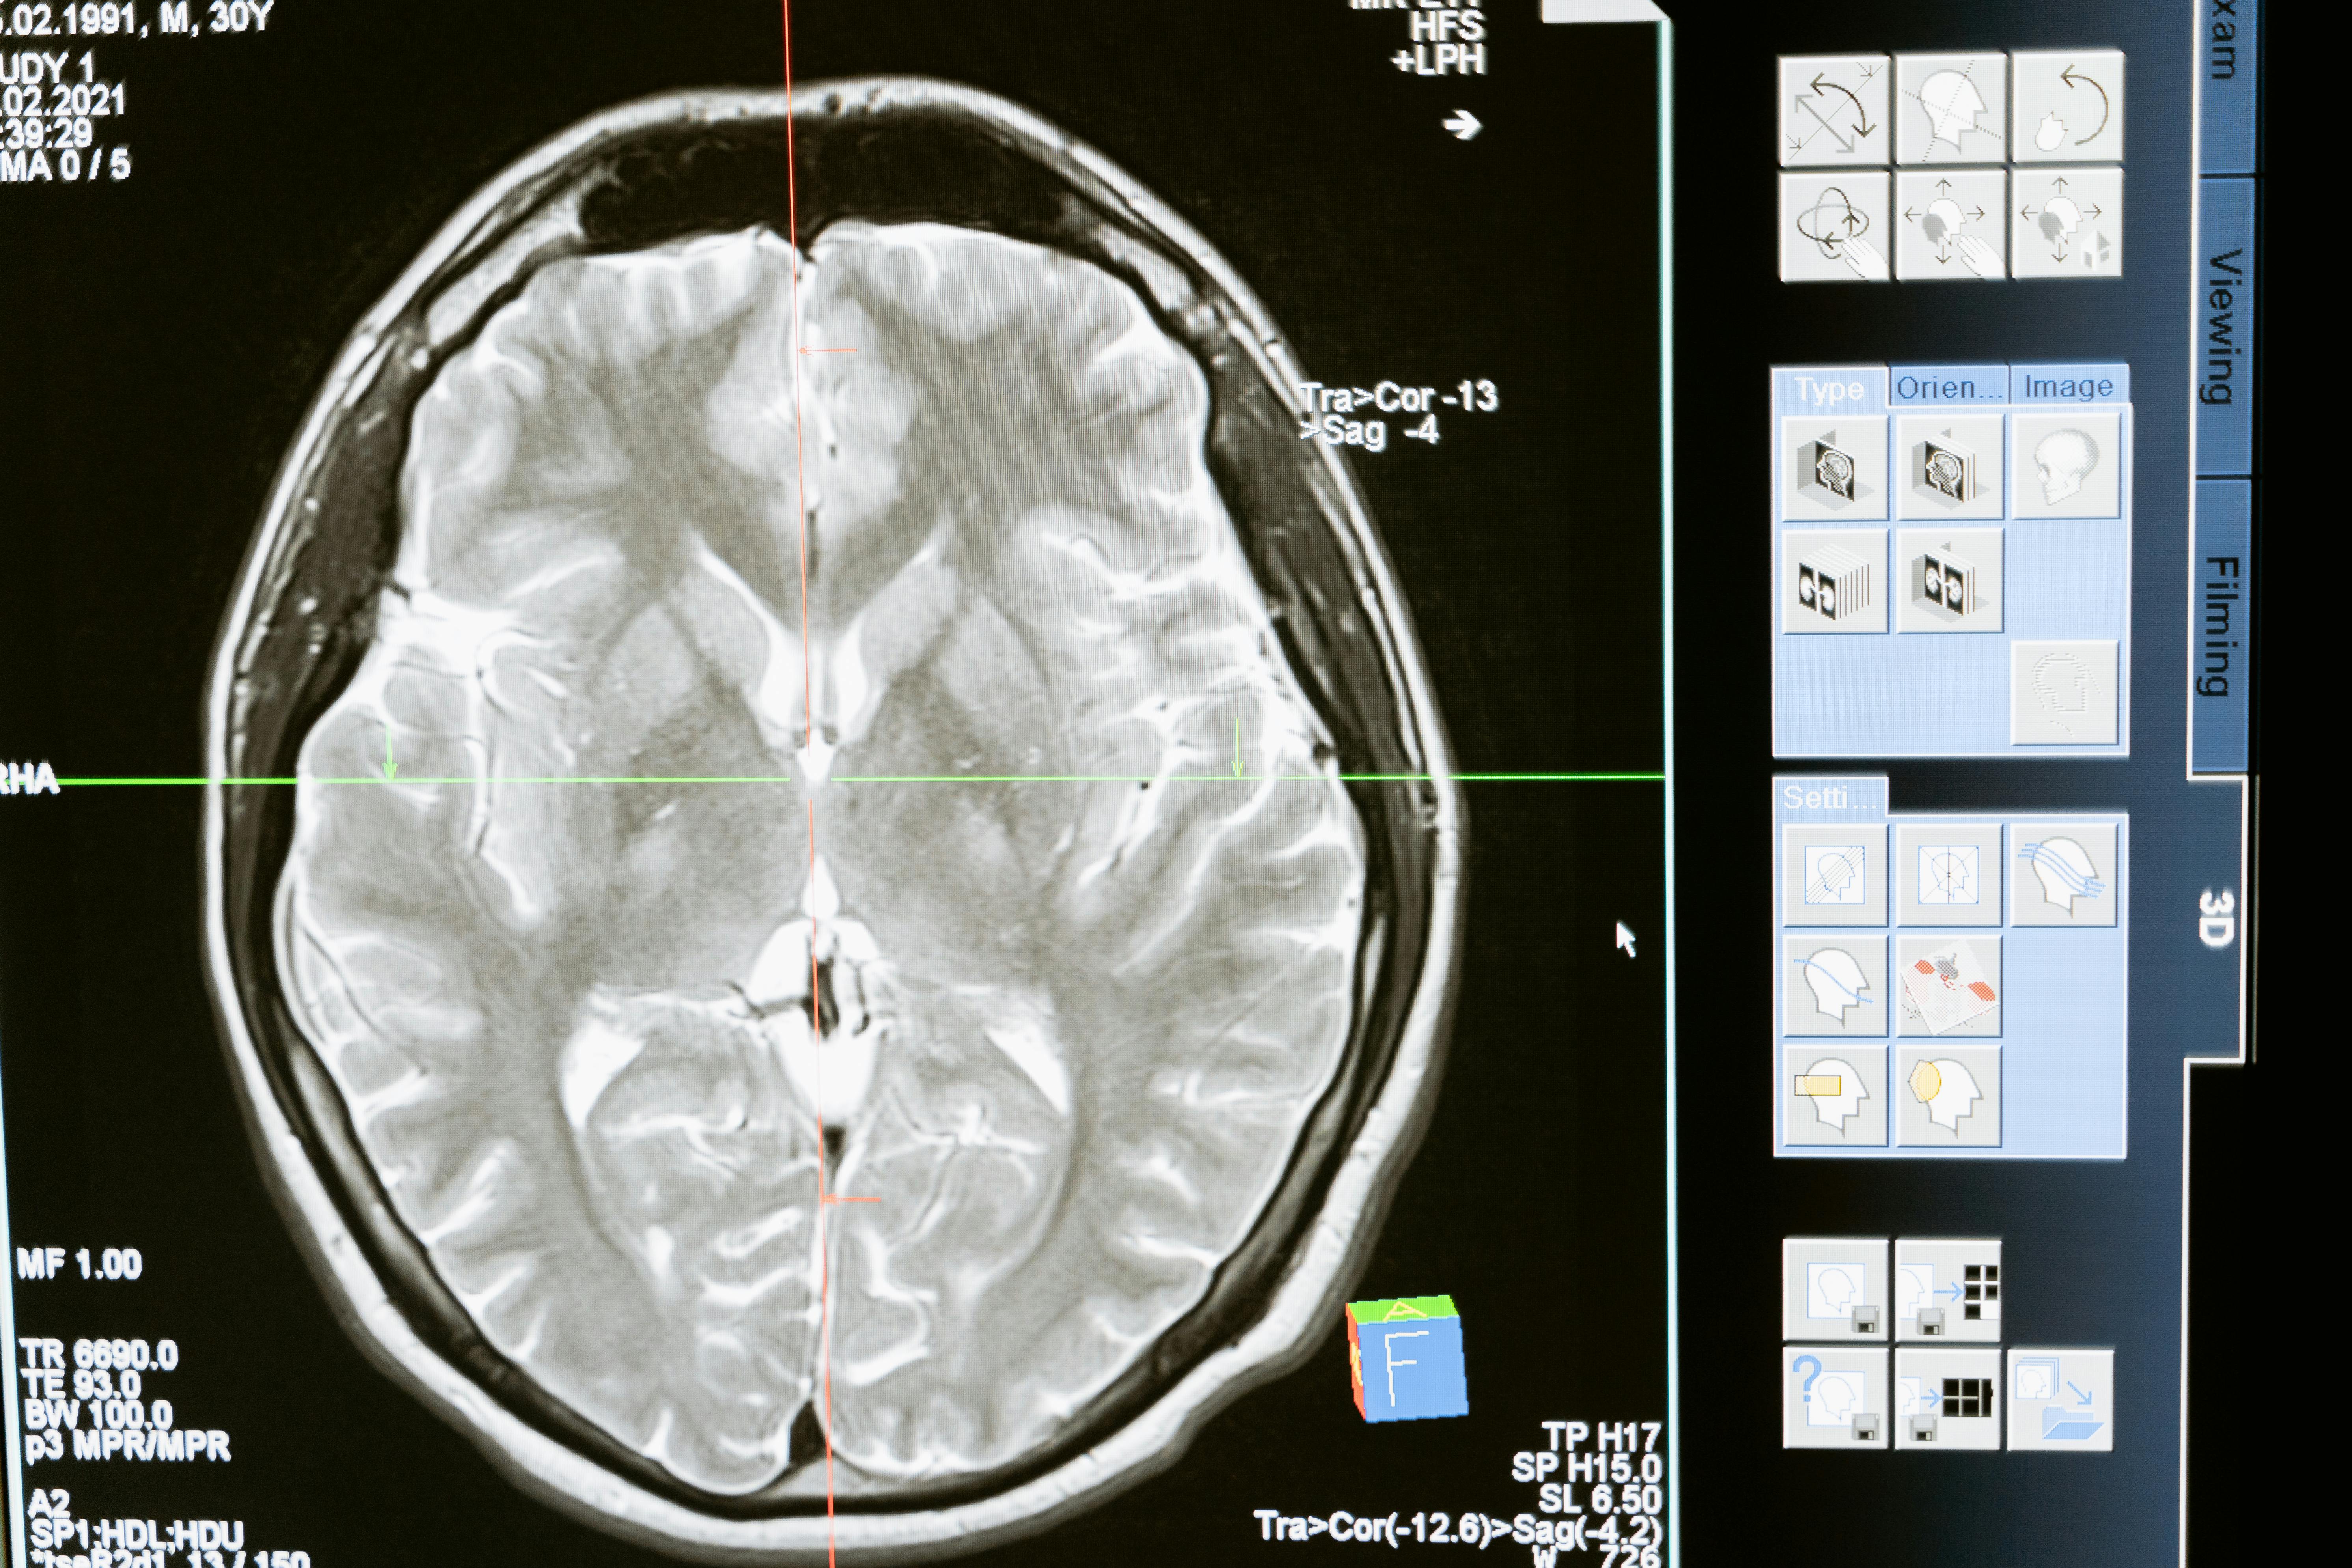

뇌출혈은 뇌 안의 혈관이 터져서 뇌 조직 내에 출혈이 생기는 상태를 말합니다. 뇌출혈은 주로 고혈압이 오래 지속됨으로써 뇌혈관 벽이 약해지고 결국 파열되는 경우가 많습니다.

실제로 국내 자료에 따르면 전체 뇌졸중 중 뇌출혈이 차지하는 비율은 약 10~15%로 알려져 있습니다. 증상은 매우 급격히 나타나며 전조증상이 없는 경우가 많고, “머리 안에서 터진 듯한 심한 두통”, 의식저하, 구토, 한쪽 팔다리 마비 등이 동반될 수 있습니다.

이처럼 뇌출혈은 빠른 손상 진행과 높은 위험성 때문에 ‘골든타임’이 없는 질환으로도 분류됩니다.

셋째, 정기적으로 뇌혈관 건강을 체크하고, 특히 가족력이 있는 경우 뇌동맥류 등 잠재 리스크에 대한 영상검사(필요시) 고려해야 합니다.